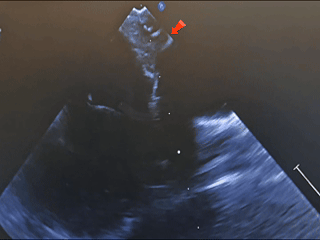

术中食道超声

经食道超声可见

第一个缺损8.06mm

术中超声:术中经食道超声可见有两个缺损,分别为8.06mm、5.63mm,和术前超声报告对比有所偏差,两缺损距离约8.48mm。